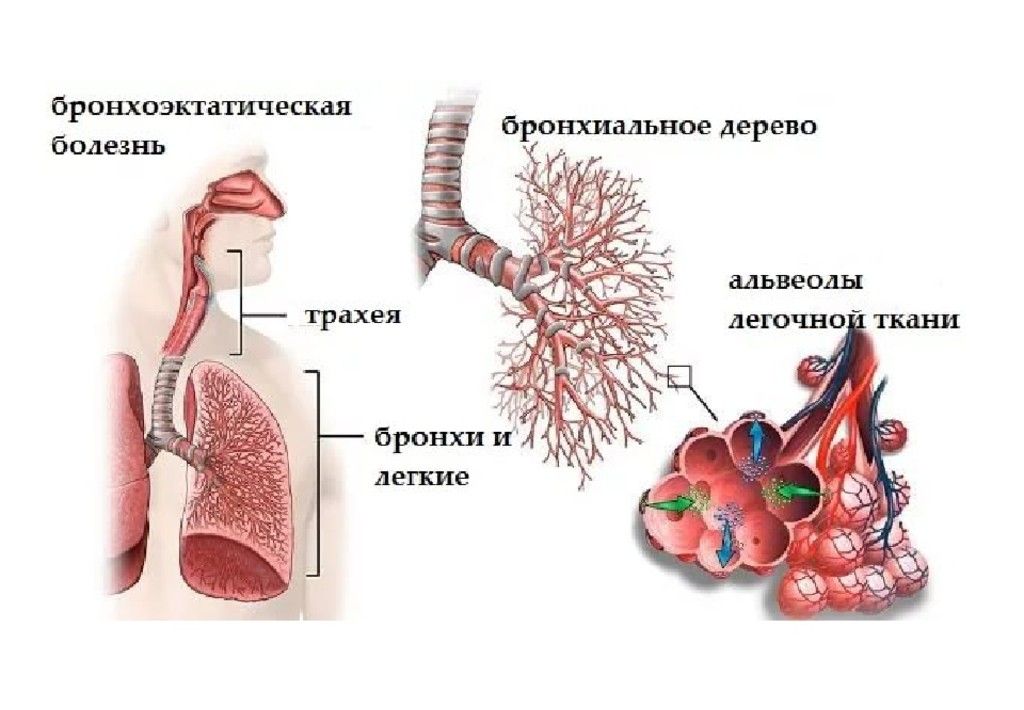

Медицинская тема: легочные осложнения при пневмонии